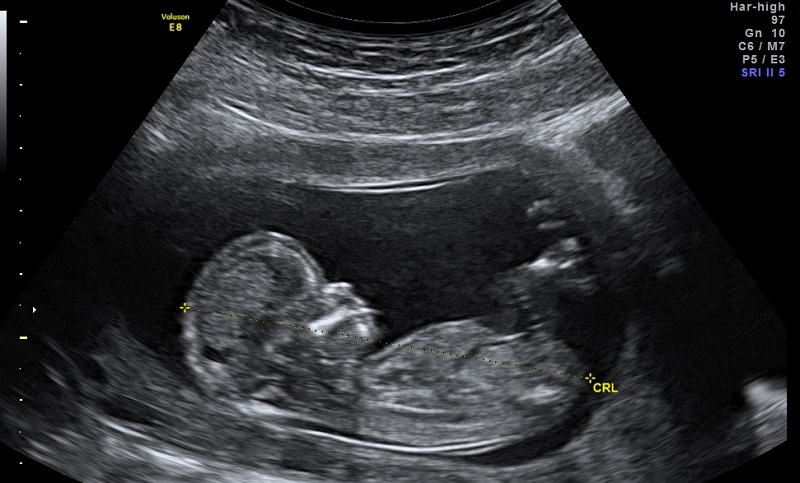

Deepecho, la startup marocaine de l’échographie prénatale

Deepecho est une startup deeptech qui parie sur une solution intelligente, produisant des résultats d'échographie fœtale avec une précision et une efficacité accrue. Zoom sur cette startup prometteuse à même de dessiner le futur du diagnostic prénatal.

L’ambition de Deepecho est noble : participer à la réduction de la mortalité prénatale et maternelle par un diagnostic échographique, plus précis et précoce, des anomalies fœtales.

En effet, la mortalité et la morbidité infantiles font des ravages puisque parmi les 130 millions de bébés qui naissent chaque année, 8 millions voient le jour avec une malformation congénitale et près de 450 meurent chaque heure. L’échographie des premier et deuxième trimestres de la grossesse est indispensable car elle permet de détecter 60 % des malformations majeures à expression précoce. Or, au Maroc, près d’un quart des femmes enceintes ne consultent pas de médecin durant leur grossesse.

De surcroît, l’échographie obstétricale est un examen complexe et chronophage qui souffre d’un inconvénient majeur : « Les mesures effectuées varient d’un opérateur à l’autre et souffrent d’un défaut de précision qui a des conséquences parfois dramatiques », précise l’équipe de Deepecho à Médias24.

Fort de ce constat, DeepEcho s’affranchit de cette limite en construisant un puissant algorithme fondé sur l’intelligence artificielle, s’adressant aux médecins pour détecter les plans biométriques standards et automatiser des mesures, avec plus de rapidité et de précision.

« La solution aide le médecin à avoir en quelques secondes un plan standard de qualité optimale et à calculer instantanément les principales mesures de biométrie fœtale comme la longueur du fémur (LF), le périmètre crânien (PC) et le périmètre abdominal (PA). Il passe d’un examen de vingt à trente minutes en moyenne à un résultat en moins d’une minute », explique l’équipe de Deepecho.